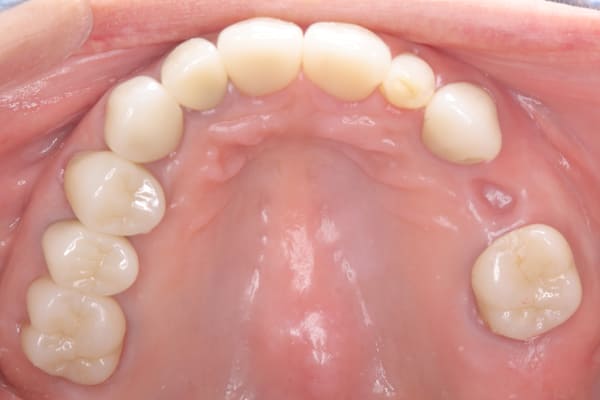

上顎治療後

下顎治療前

-

下顎治療後

治療前の入れ歯の奥歯は、治療後の義歯と比較しても分かるように、歯が削れ平らになった状態です。

これにより奥歯のかみ合わせは低くなり、前歯のみが強くあたり、かみ合わせにより上の前歯大きな負担がかかっていたことにより、上の前歯が折れたことが考えられます。